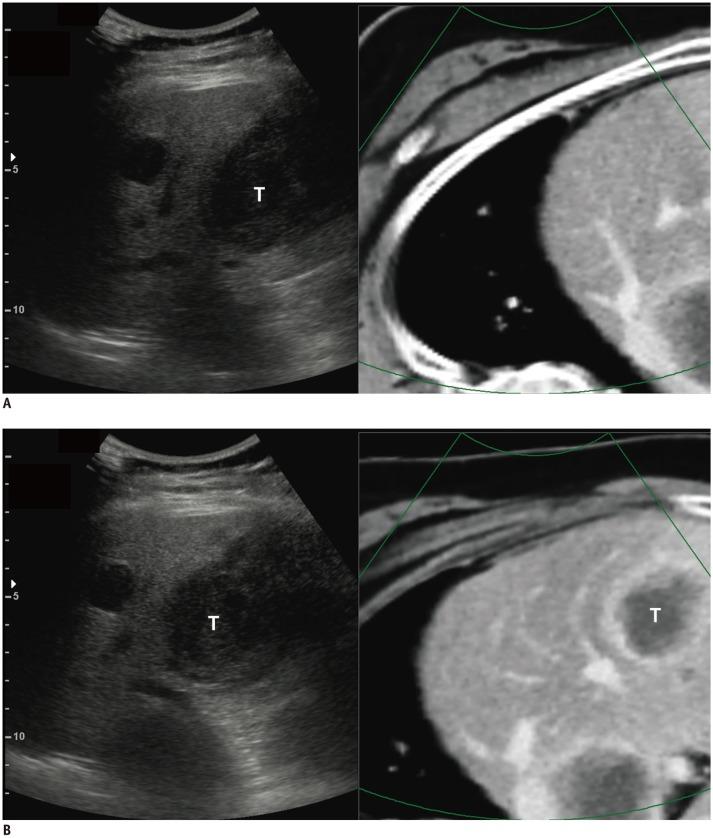

To assess whether virtual expiratory (VE)-computed tomography (CT)/ultrasound (US) fusion imaging is more effective than conventional inspiratory (CI)-CT/US fusion imaging for hepatic interventional procedures.

This prospective study was approved by the Institutional Review Board, and informed consent was obtained from each patient. In total, 62 patients with focal hepatic lesions referred for hepatic interventional procedures were enrolled. VE-CT images were generated from CI-CT images to reduce the effects of respiration-induced liver motion. The two types of CT images were fused with real-time US images for each patient. The operators scored the visual similarity with the liver anatomy upon initial image fusion and the summative usability of complete image fusion using the respective five-point scales. The time required for complete image fusion and the number of point locks used were also compared.

In comparison with CI-CT/US fusion imaging, VE-CT/US fusion imaging showed significantly higher visual similarity with the liver anatomy on the initial image fusion (mean score, 3.9 vs. 1.7; < 0.001) and higher summative usability for complete image fusion (mean score, 4.0 vs. 1.9; < 0.001). The required time (mean, 11.1 seconds vs. 22.5 seconds; < 0.001) and the number of point locks (mean, 1.6 vs. 3.0; < 0.001) needed for complete image fusion using VE-CT/US fusion imaging were significantly lower than those needed for CI-CT/US fusion imaging.

VE-CT/US fusion imaging is more effective than CI-CT/US fusion imaging for hepatic interventional procedures.

评估虚拟呼气(VE)-计算机断层扫描(CT)/超声(US)融合成像是否比传统吸气(CI)-CT/US 融合成像更有利于肝脏介入治疗。

本前瞻性研究经机构审查委员会批准,并获得每位患者的知情同意。共纳入 62 例因肝脏局灶性病变而行肝脏介入治疗的患者。从 CI-CT 图像中生成 VE-CT 图像,以减少呼吸引起的肝脏运动的影响。为每位患者将两种类型的 CT 图像与实时 US 图像融合。操作人员在初始图像融合时根据肝解剖结构的视觉相似性以及完全图像融合的综合可用性对图像融合进行评分,分别采用五分制。还比较了完全图像融合所需的时间和使用的点锁数量。

与 CI-CT/US 融合成像相比,VE-CT/US 融合成像在初始图像融合时具有更高的肝解剖结构的视觉相似性(平均评分,3.9 对 1.7;<0.001)和更高的完全图像融合的综合可用性(平均评分,4.0 对 1.9;<0.001)。VE-CT/US 融合成像完成图像融合所需的时间(平均 11.1 秒对 22.5 秒;<0.001)和点锁数量(平均 1.6 对 3.0;<0.001)明显少于 CI-CT/US 融合成像。

VE-CT/US 融合成像比 CI-CT/US 融合成像更有利于肝脏介入治疗。